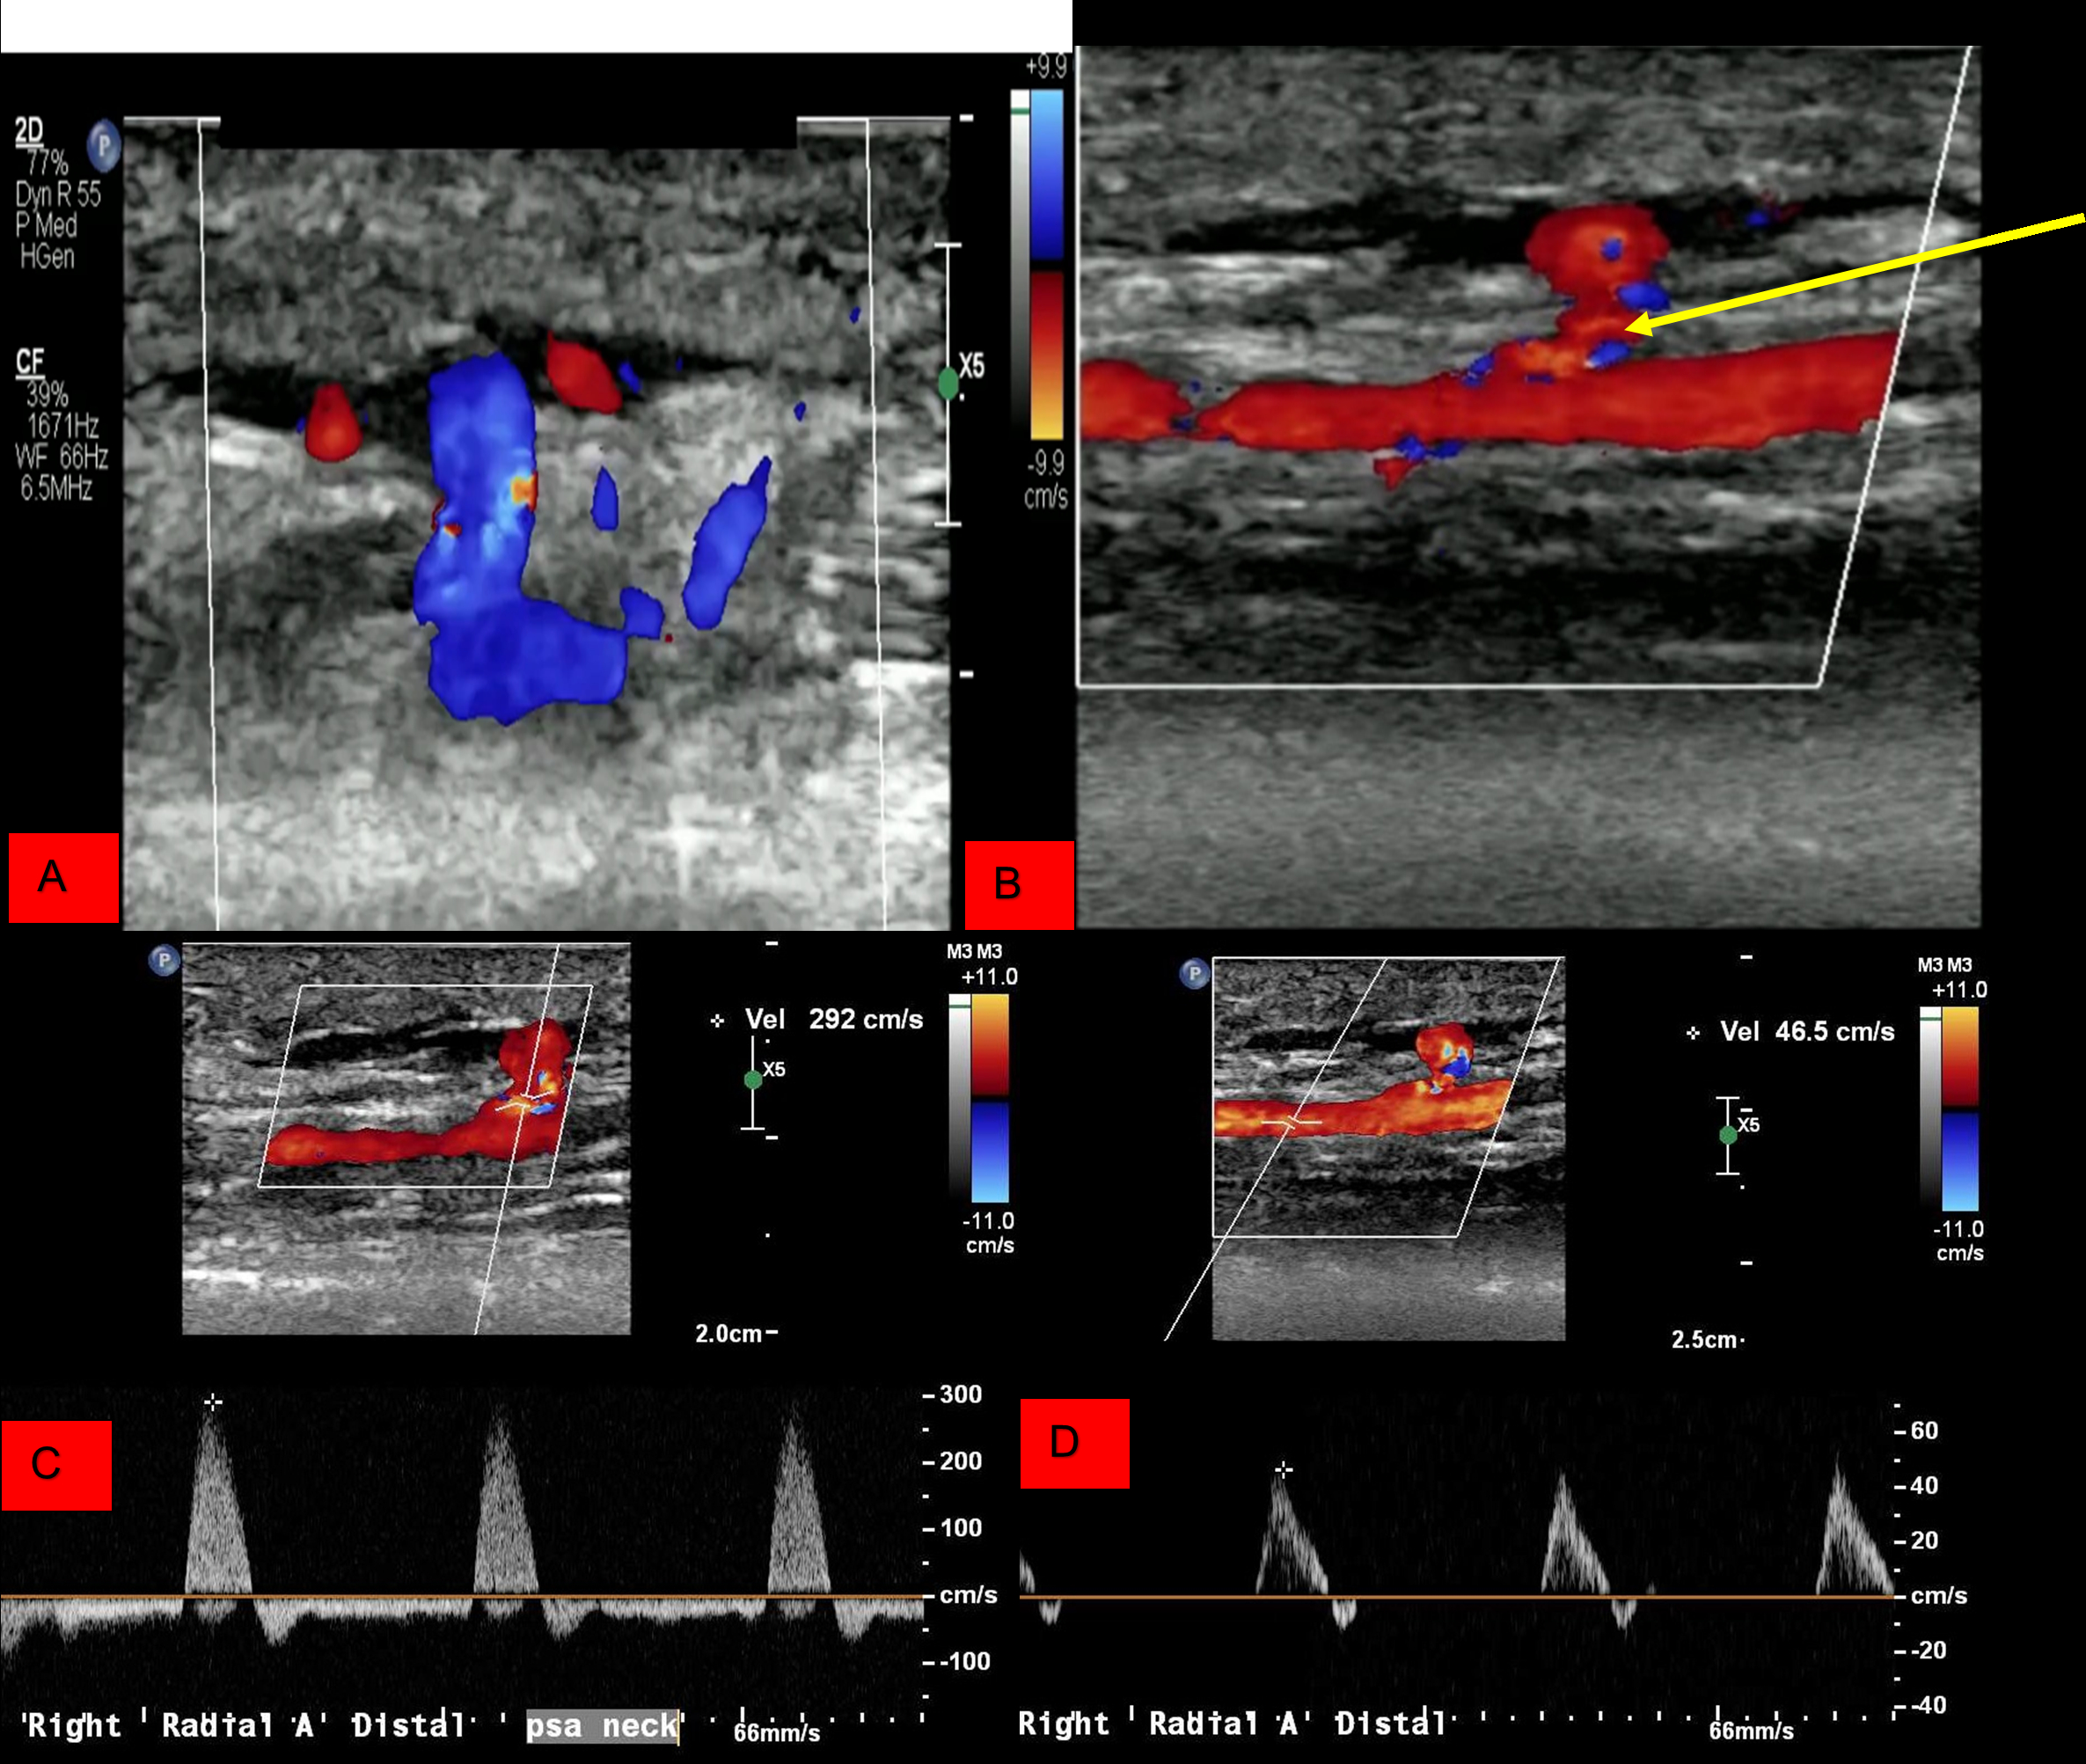

Radial Artery Pseudoaneurysm Following Transradial Cardiac Catheterization: A Systematic Review and Case Report

Transradial cardiac catheterization (TRC) is recommended for patients with acute coronary syndrome over femoral artery catheterization. Randomized controlled trials show TRC has significantly lower rates of bleeding, vascular complications, and mortality in high-risk acute coronary syndrome patients. However, vascular complications like radial artery spasm, occlusion, arteriovenous fistula, perforation, and pseudoaneurysm (PSA) can still occur. Despite TRC's widespread adoption, recent data summarizing radial artery pseudoaneurysm post-TRC is lacking.

From 3,262 records, 43 studies were selected, involving 67 patients (58.8% female, median age 73.5 years). Hypertension (39.5%) and atrial fibrillation (27.9%) were the most common comorbidities. Percutaneous interventions like stenting and angioplasty caused 58.1% of cases; diagnostic catheterizations accounted for 37.2%. Ultrasonography diagnosed 83.7% of cases. Symptoms appeared a few hours to four months post-TRC, with pulsatile mass (21.4%) and swelling (14.3%) being the most common, and pain and ecchymosis at 2.4% each. More than half of the patients (51.2%) required surgical intervention, but 66.7% recovered without deficits. Severe complications were rare, affecting fewer than 5%.

A literature review of 43 articles with 67 patients suggests older female patients with hypertension may be more prone to radial artery pseudoaneurysm post-TRC. It typically presents as a pulsatile, painful swelling detectable by ultrasound. This complication precludes the use of the radial artery as a conduit for coronary artery bypass grafting. The review highlights the importance of vigilant post-catheterization monitoring to enable early detection and treatment.